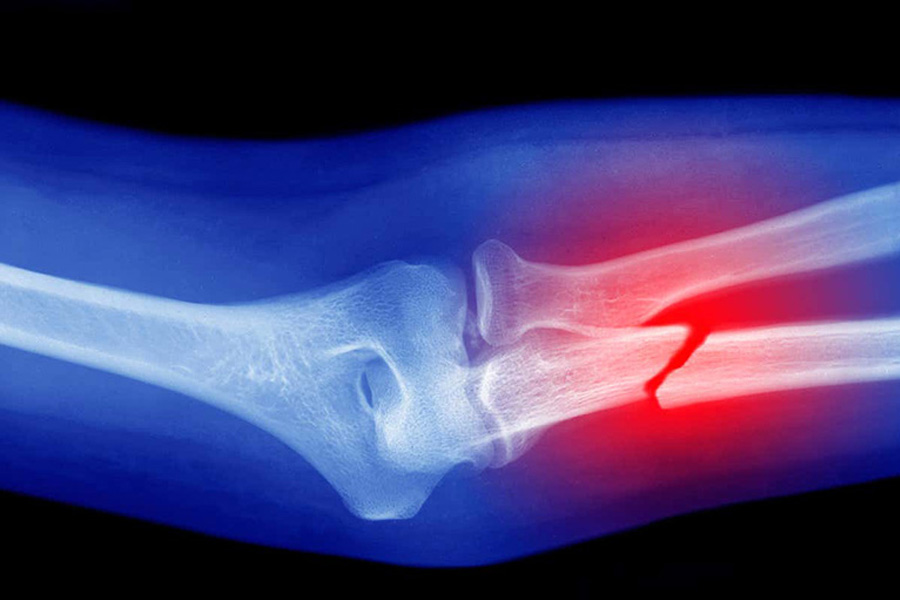

Gãy xương là sự phá hủy đột ngột của các cấu trúc bên trong xương gây ra các tổn thương và làm gián đoạn về truyền lực qua xương. Tình trạng xương mất tính liên tục và hoàn chỉnh do ngoại lực hoặc bệnh lý gây ra. Gãy xương gồm: gãy đầu xương, gãy xương hoàn toàn, gãy xương không hoàn toàn, gãy xương kín, gãy xương hở,...

Bệnh gãy xương kín